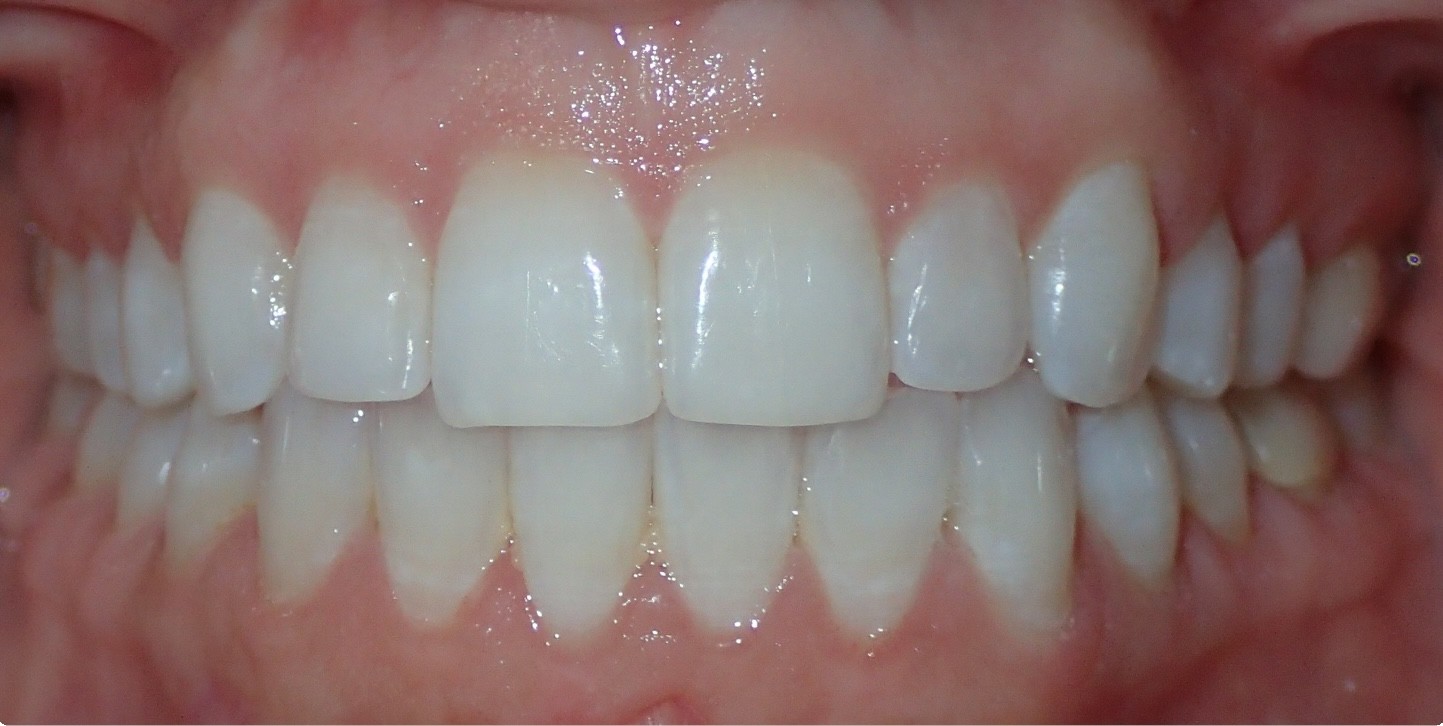

Final results

INTRAORAL